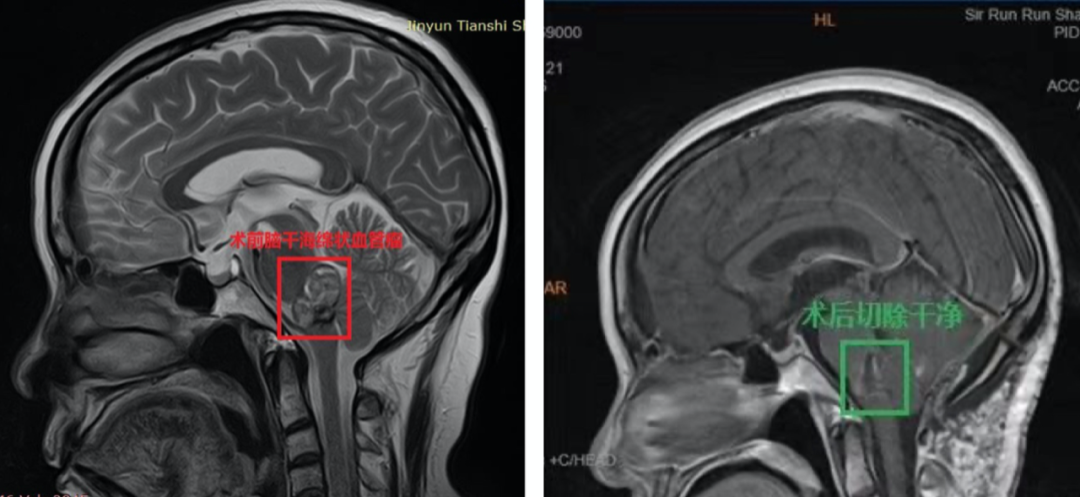

1、术前诊断:脑干脑桥海绵状血管瘤,6次脑干出血活动期,压迫四脑室

3、手术结果:显微镜下全切肿瘤,肿瘤切除历时约1.5小时,手术顺利。

术后48小时内MR复查显示肿瘤全切